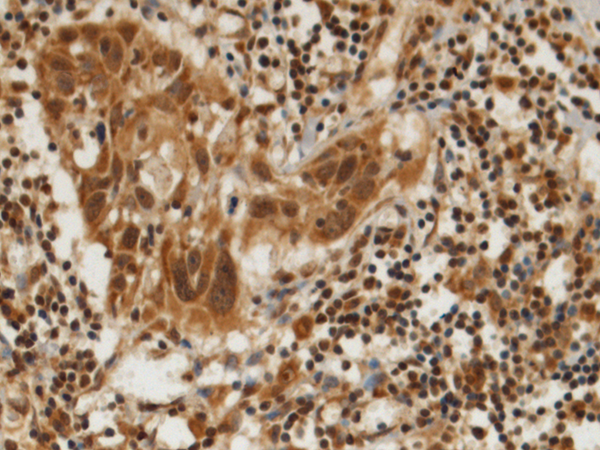

IHC positive control: |

Human esophagus cancer and Human gastric cancer |